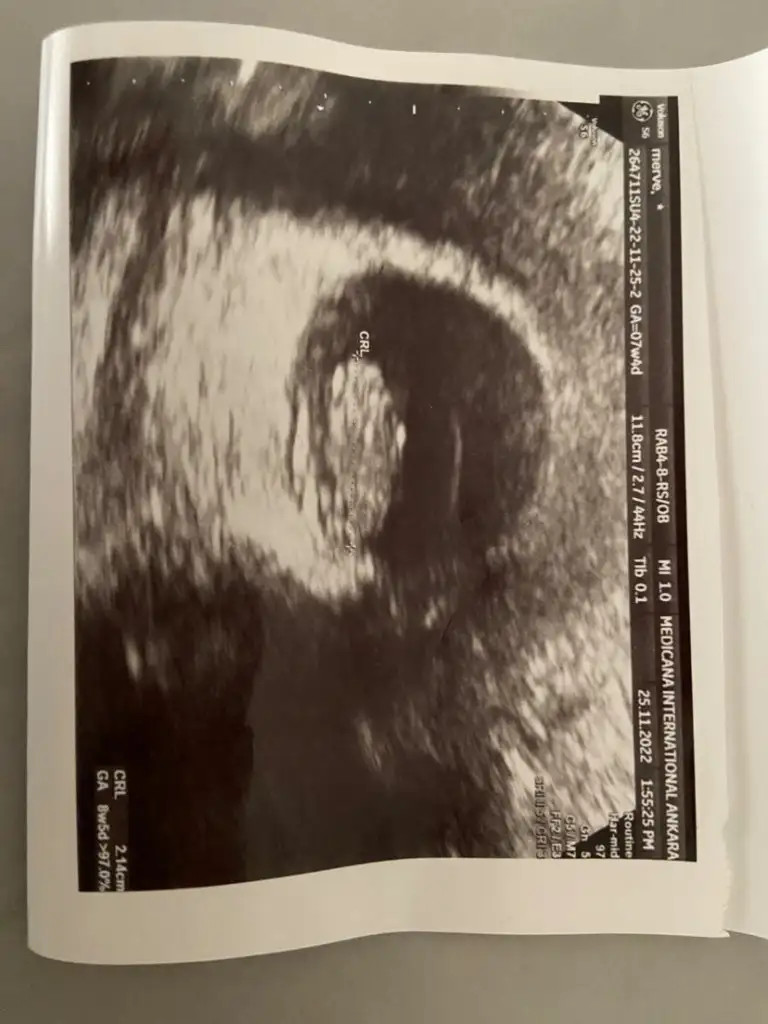

Heh işte böyle fotolar lazım banaEki Görüntüle 3202507 Ya da bu var

Her türlüsü mevcut fotoların da işte ben de ah bi anlasamHeh işte böyle fotolar lazım banaKız gibi geldi canım bana karından ultrasonsa eğer

Gönlünüzdeki sağlıkla olsun inşallahHer türlüsü mevcut fotoların da işte ben de ah bi anlasamevet hepsi karındandı aayy hadi inşallah ya çok teşekkür ederimm